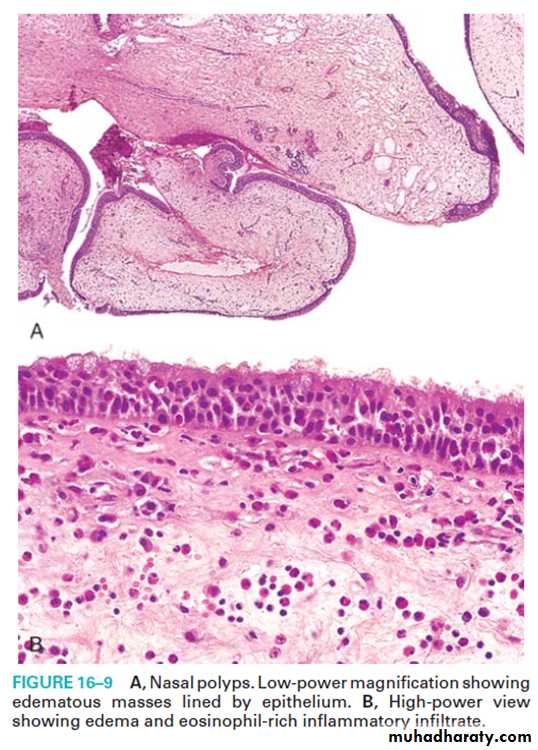

The mucosa is thickened, polypoidal & covered by mucopurulent exudates & may form nasal polyp .Epistaxis

(d) nasal polyps.